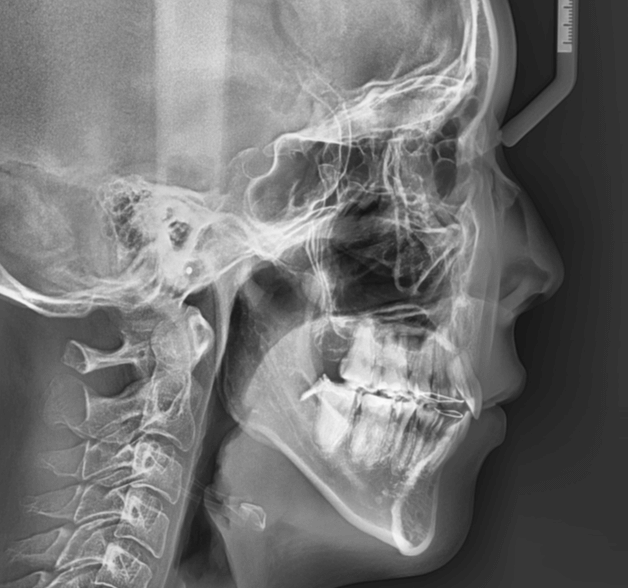

| 年齢・性別 | 22歳女性 |

|---|---|

| 主訴 | 上下顎前歯部に開咬と口元の突出感を気にされて来院された22歳女性。咬み合わせや審美的な改善を希望されていました。 |

| 治療期間・回数 | 3年9ヶ月・32回 |

| 費用 | 930,000円 |